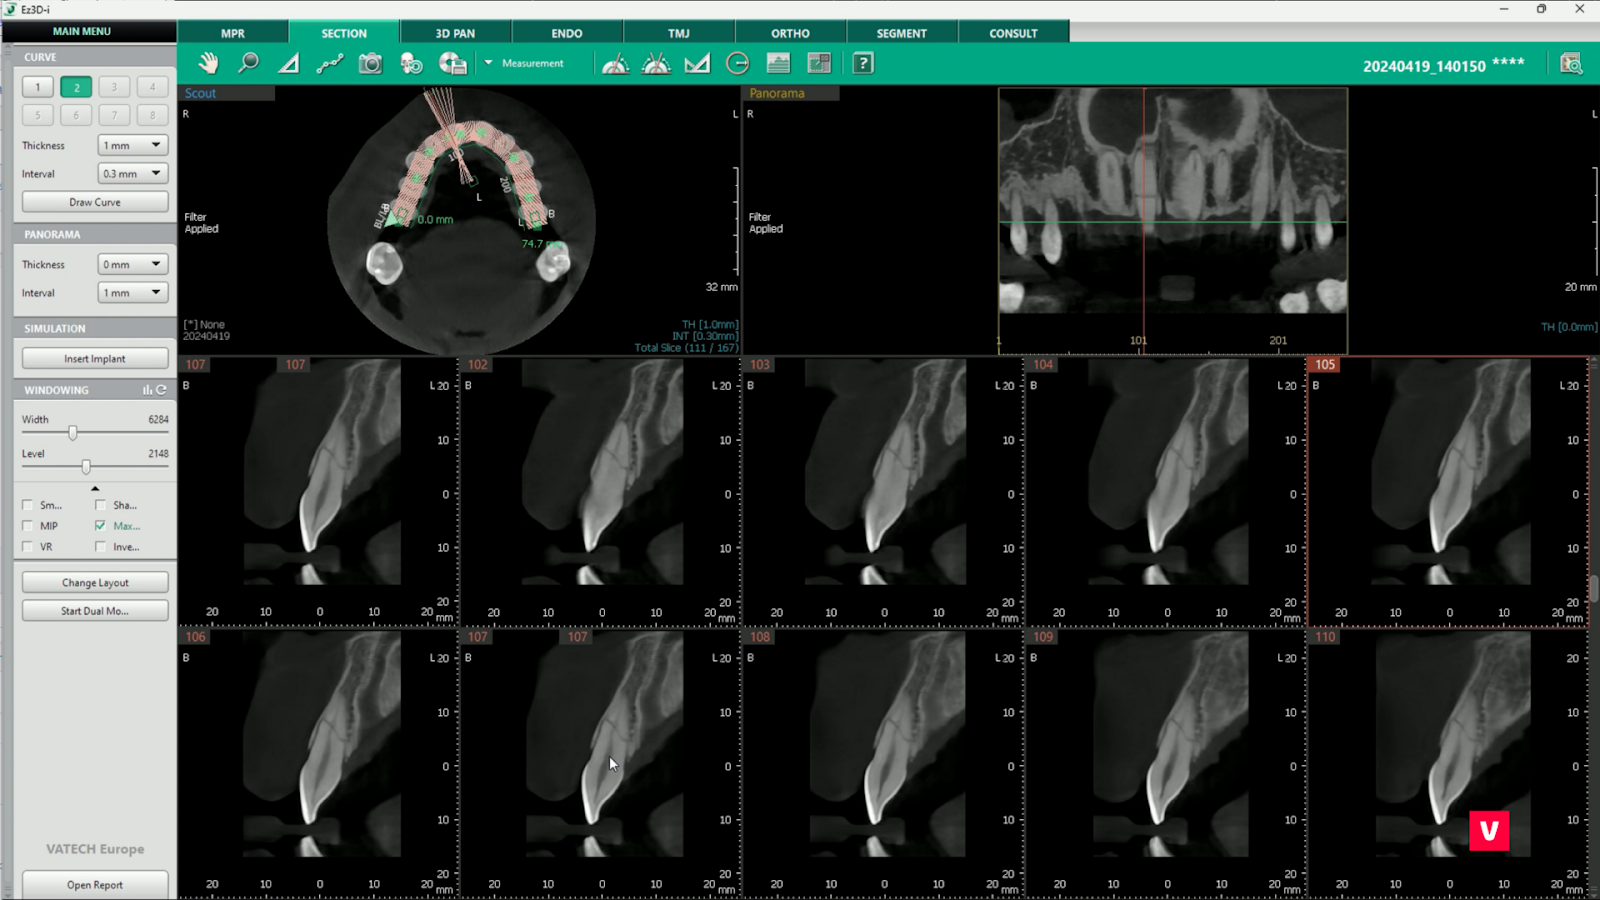

1. Reconstrucția unei secțiuni 2D de-a lungul arcadei dentare

1.Reconstrucția unei secțiuni 2D

Tabul SECTION poate oferi o mulțime de informații utile de diagnosticare. Nu numai că oferă o perspectivă amănunțită asupra dinților, dar ajută și la găsirea canalului mandibular și, prin urmare, este de mare ajutor în procesul de plasare a implanturilor.

Pentru a începe procesul de reconstrucție se folosește funcția „Draw Arcade”. Acest instrument ne ajută la reconstrucția zonelor dorite deoarece, spre deosebire de funcția MPR, unde imaginile sunt realizate conform liniilor prestabilite, putem determina singuri linia arcadei.

Dacă folosim și funcția care ne permite să reglăm grosimea imaginii arcadei, nu vom rata niciun detaliu oricât de mic despre starea dintelui. De asemenea, putem verifica ușor și sigur canalul mandibular inferior.

Procesul de desenare a arcadei este foarte simplu datorită opțiunii de a adăuga elemente vizuale, de a ajusta lungimea și de a o muta în poziția dorită.

În cazul pacientului al cărui studiu de caz îl analizăm, tăierea în plan coronal a evidențiat imediat fractura dintelui dureros, în timp ce imaginea OPG normală nu a putut evidenția problema la fel de clar.

Astfel, datorită funcției SECTION, medicul stomatolog a economisit timp și a obținut un diagnostic corect.